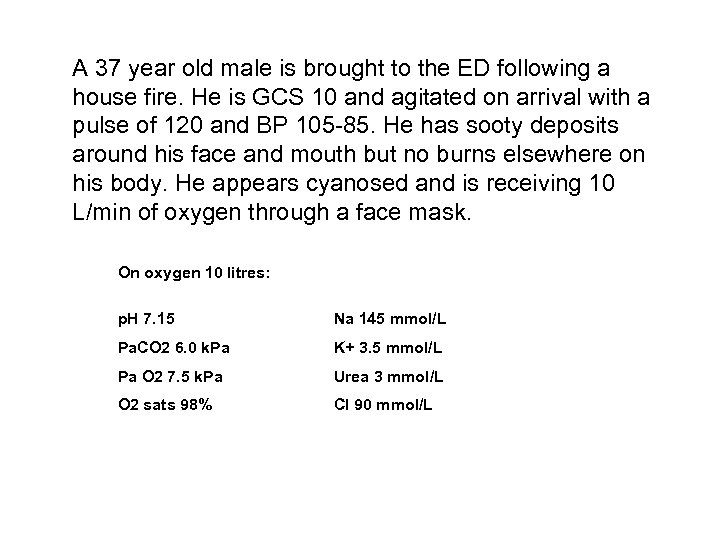

A 37 year old male is brought to the ED following a house fire. He is GCS 10 and agitated on arrival with a pulse of 120 and BP 105 -85. He has sooty deposits around his face and mouth but no burns elsewhere on his body. He appears cyanosed and is receiving 10 L/min of oxygen through a face mask. On oxygen 10 litres: p. H 7. 15 Na 145 mmol/L Pa. CO 2 6. 0 k. Pa K+ 3. 5 mmol/L Pa O 2 7. 5 k. Pa Urea 3 mmol/L O 2 sats 98% Cl 90 mmol/L

• Calculate the anion gap including your workings (1 mark) • What is the explanation for this result in this patient? (1 mark) • What empirical treatment might you consider? (1 mark)